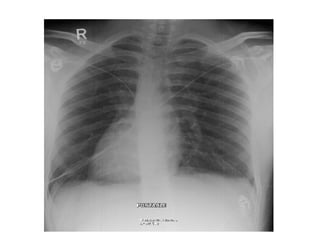

This document contains medical terms and questions related to cardiology board exams. It discusses cases involving Brugada syndrome, ventricular fibrillation treated with an implantable cardioverter-defibrillator, hyperacute anterior ST elevation myocardial infarction, pericarditis, various arrhythmias including Wolff-Parkinson-White syndrome, ectopic atrial rhythm, junctional rhythm, low voltage ECG, left bundle branch block, ventricular tachycardia, and atrial flutter.